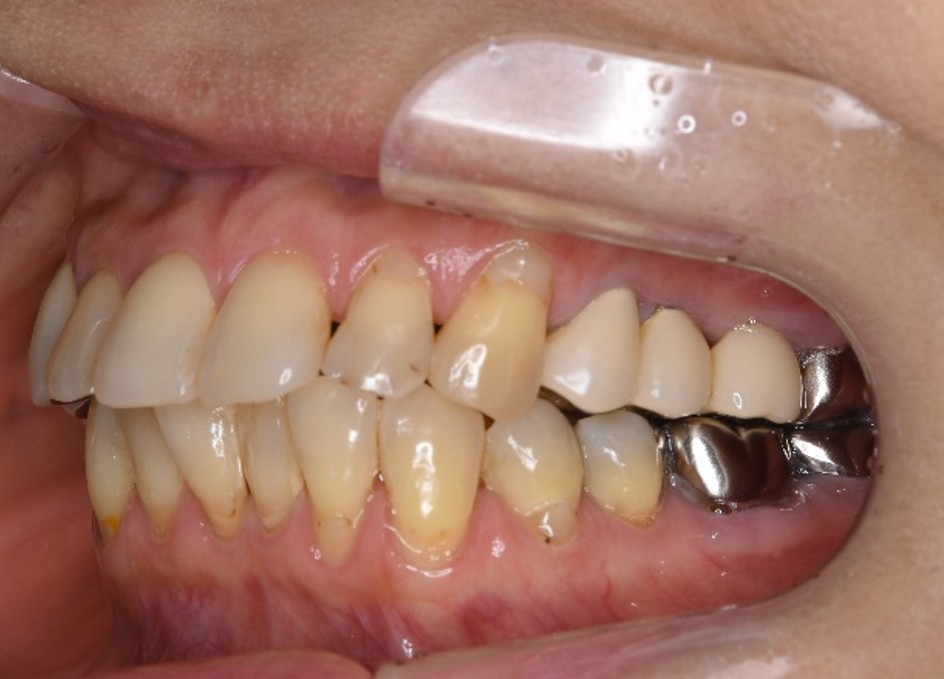

治療前